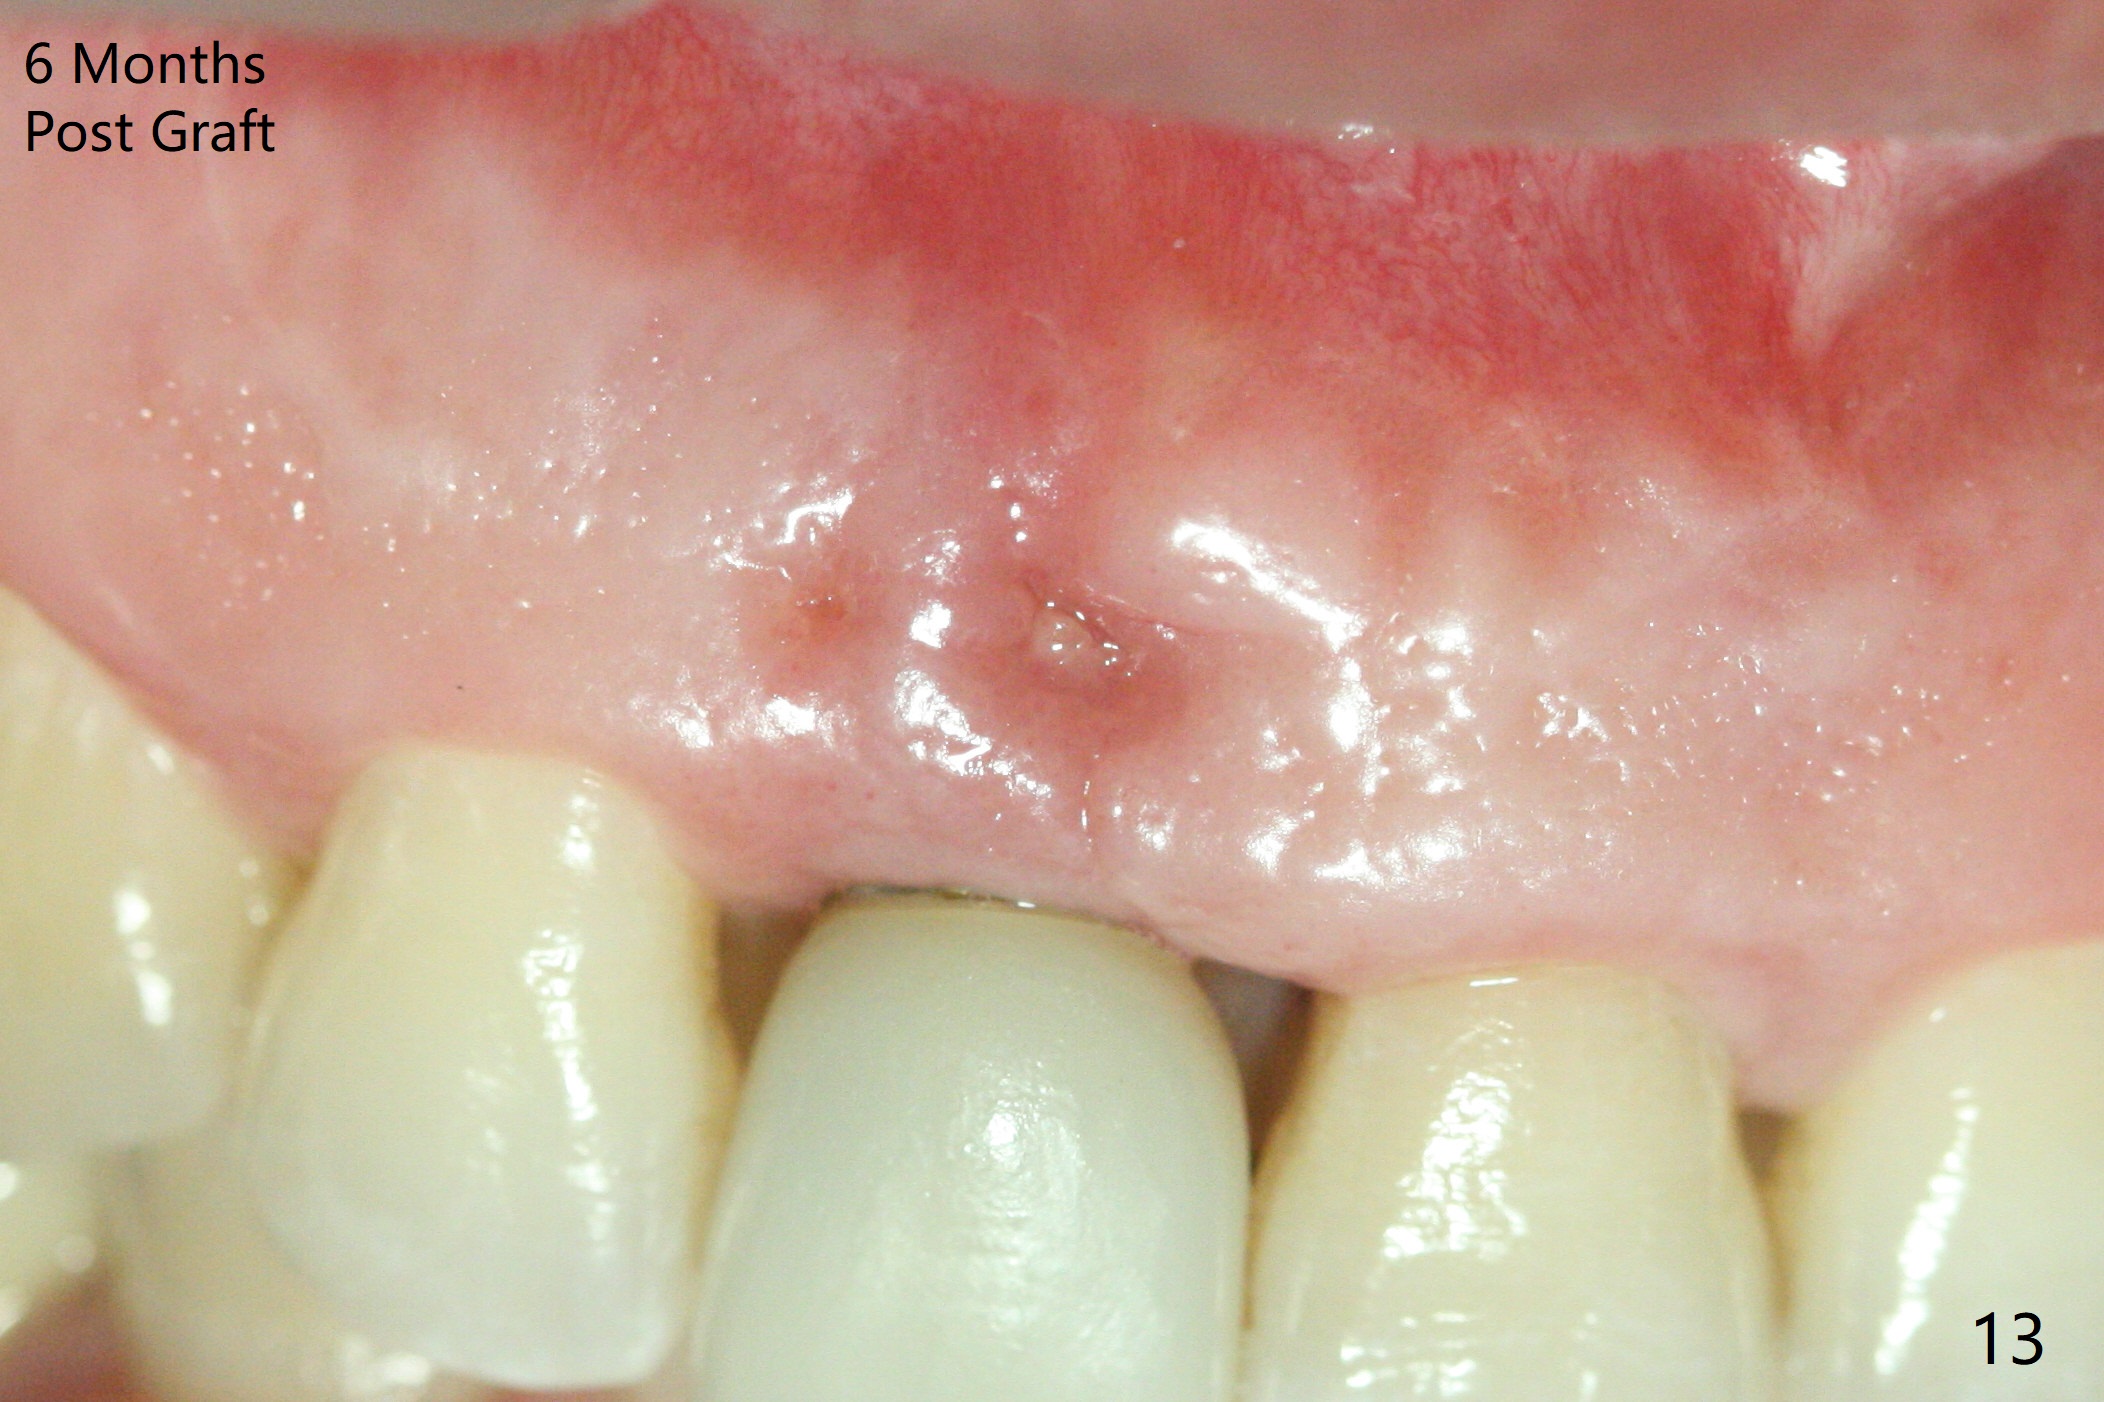

The patient returns because of purulent exudate from the buccal fistula (Fig.1 *) 1 year 9 months postop (1 year 3 months post cementation). Preop CT shows buccal thread exposure (Fig.2 arrowheads). To prevent postop gingival recession, a semilunar incision is made between the fistula and the gingival margin (Fig.3). After removal of granulation tissue (Fig.4), allograft in sticky bone form is packed (Fig.5). Following placement of PRF membrane and 6-month collagen membrane, the wound is closed (Fig.6). Since the implant (Fig.7 I) thread exposure is within bone (B) boundary (Fig.8 red dashed line), bone graft with PRF should be able to take care of periimplantitis (A: abutment). To prevent periimplantitis in similar situation, the immediate implant should be placed deep (not necessarily long, 18 mm) and narrower (3.5 mm instead of 3.8 mm). The defective buccal plate should be repaired with sticky bone and collagen membrane with incision if necessary. The wound does not dehisce 1 week postop (Fig.9) or 3 weeks postop (Fig.10, immediately post suture removal). Although bone graft seems to stay in place 6 months postop (Fig.11,12), the patient complains of bone graft expulsion sometimes. The buccal gingiva has deficiency (Fig.13). To fix it, make a remote incision (Fig.14 black line) and dissect before gingiva graft (Fig.15 dashed line). After removal of crown/abutment, the sinus track and implant surface are treated with Waterlase. A shorter cuff abutment is placed (4.5x5(4 to 3) mm) with a new provisional. The patient feels better with reduced sinus track 2 weeks postop (Fig.16).